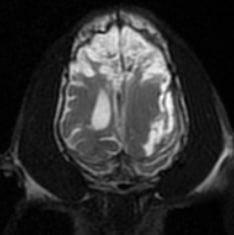

Пациент: 4-месячный щенок (метис). Субдуральная гематома, возникшая в результате закрытой черепно-мозговой травмы (ЗЧМТ). В данном случае с целью устранения гематомы и предотвращения дальнейшего сдавления мозговых структур была выполнена краниотомия.В связи с изменениями, опосредованными ЗЧМТ и смещением структур головного мозга вправо, возникла необходимость пересмотра плана проведения операции и возможного расширения хирургического доступа у данного пациента. Для обеспечения адекватной анальгезии пациента было принято решение о проведении блокады тройничного нерва (рис. 23, 24).

Схема анестезии: премедикация – дексмедетомидин; индукция – пропофол; поддержание – изофлуран.

Анальгезия: блокада тройничного нерва + блокада большого затылочного нерва (ропивакаин + дексаметазон)

У данного пациента не было выявлено отклонений в показателях витальных функций на протяжении всего оперативного вмешательства. Единственным исключением стало гемодинамически незначимое снижение ЧСС на 20–30% после завершения доступа к головному мозгу, которое обусловлено вегетативными реакциями нервной системы. Ввиду сохранения продуктивного спонтанного дыхания ИВЛ данному пациенту не проводилась. В ходе операции и в раннем послеоперационном периоде системное применение анальгетиков не потребовалось (рис. 25).